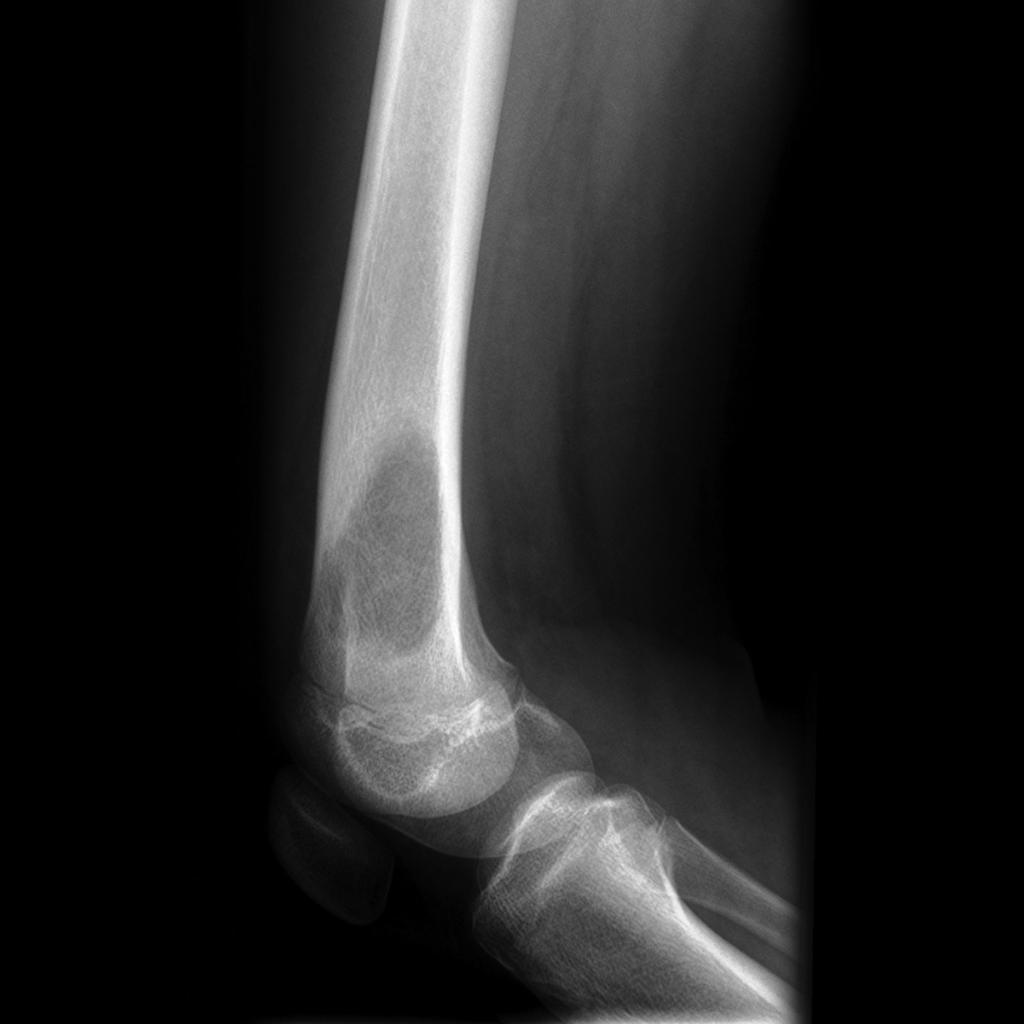

what is seen on X ray

cortical destruction, periosteal reaction, new bone formation and extension into surrounding soft tissue

what is a periosteal reaction

formation of new bone in response to periosteum (injury to)